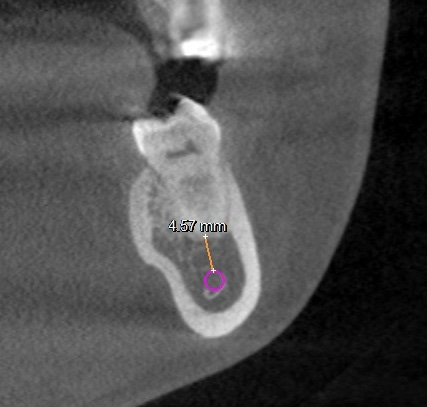

All molar teeth were evaluated in 3 planes (sagittal, axial and coronal) to determine the shortest linear distance between the root apex and the superior cortical border of MC (Figure 1). Distances <1.00 mm were classified as very close to MC (Figure 2).28 Distances ≥1.00 mm were considered distant from MC (Figure 3).28 When the root apex was in intimate contact with or invading MC, the distance was recorded as 0 mm (Figure 4).